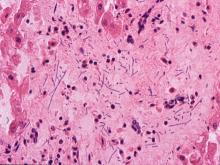

脾臟:大量紅血球蓄積無法辨識淋巴濾泡,僅殘存脾小樑、脾動脈及少數淋巴球聚集成團,在大區域出血區可見一對呈竹節樣排列之齊頭桿菌,但皆無明顯之炎症反應(圖6)。 2.

肝:肝竇狀隙擴張內充滿紅血球、肝索排列凌亂,近門脈區之肝細胞呈空泡化,可見少數短桿菌浸潤於竇狀隙中,門脈區之肝組織及血管內則可見大量細菌浸潤,其特性皆為兩個或三、四個呈鏈狀排列,無明顯之炎症反應(圖7)。 6.

血液抹片經Wright's stain 可見大量齊頭短桿菌呈串狀或兩兩成對狀排列(圖8)。 2.